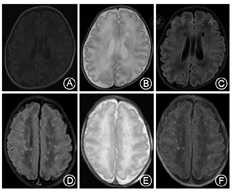

两组患儿头颅MRI检查EOP形式均以非囊性EOP为主。NEC组患儿发生EOP 29例,其中MRI结果为非囊性EOP 26例(89.7%),囊性EOP 3例(10.3%);对照组发生EOP 36例,其中非囊性EOP 23例(63.9%),囊性EOP 13例(36.1%)。NEC组非囊性EOP比例高于对照组,差异有统计学意义(OR= 1.403,95%CI 1.066~1.847 ,χ2=5.746,P=0.017)。具体情况见表2、图1。

本研究显示,NEC组EOP患儿的头颅MRI表现主要以非囊性损伤为主(89.7%),这种损伤头颅B超难以发现,需要MRI检查进行诊断。NEC早产儿患EOP比例较高,且MRI表现以非囊性EOP为主,需加强早期头颅MRI评估及神经预后评估随访,早期干预,以改善预后。